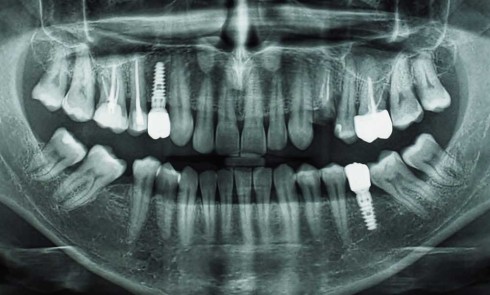

Article réservé à nos abonnés Implantation et profil d’émergence : évolution des concepts

Depuis la découverte de l’ostéointégration, le monde scientifique de l’implantologie a successivement porté son attention sur la compréhension du processus...